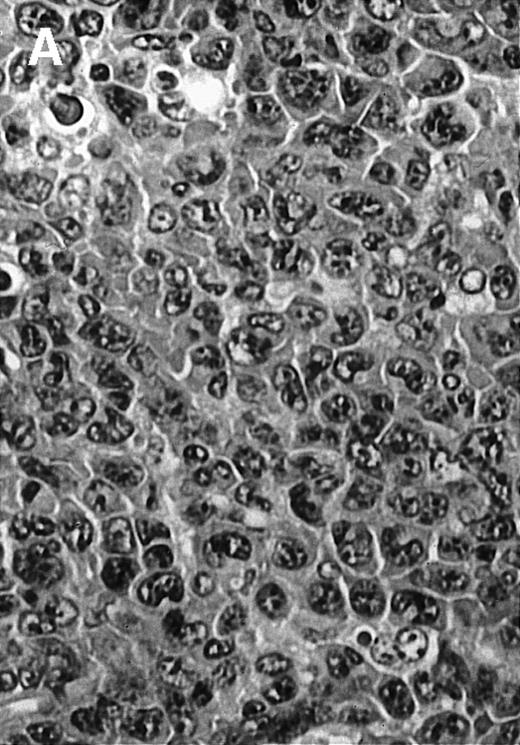

To explore the mechanisms of the protection from BCL growth, histologic analysis was performed on tumor tissue from mice treated with ST40L, ST, or PBS alone. In the mice treated with PBS alone, no cellular infiltrate expressing FasL was observed in the surrounding tissues and inside the BCL region (Figure 4A and D). In contrast, infiltrating lymphocytes expressing FasL were observed around the vessels and also scattered in the smaller tumor tissues in the mice treated with ST (Figure 4B and E). Small hard nodules (2-5 mm in diameter) were observed at the SC injection sites of the long-term survival mice that had been treated with ST40L. On histologic analysis, these small nodules were confirmed to be the result of an accumulation of lymphocytes, and not BCL cells (Figure 4C). These lymphocytes were also found to be strongly positive for FasL expression (Figure 4F). On the other hand, lymphocytes infiltrating in the nodules were stained by either CD4+ Ab or CD8+ Ab, but the ratio of CD4+ and CD8+ cells was not 1-sided (data not shown).

Histologic analysis of A20 tumors excised 21 days postchallenge from BALB/c mice immunized with ST40L.

(A) HE stain of a BCL region in a mouse treated with PBS alone. (B) HE stain of a smaller BCL region in a mouse treated with ST. (C) HE stain of a small hard nodule at the SC injection site in a mouse treated with ST40L. (D) Fas ligand staining of a BCL region in a mouse treated with PBS alone. (E) Fas ligand staining of a BCL region in a mouse treated with ST. (F) Fas ligand staining of a small hard nodule at the SC injection site in a mouse treated with ST40L. Original magnifications are ×400.